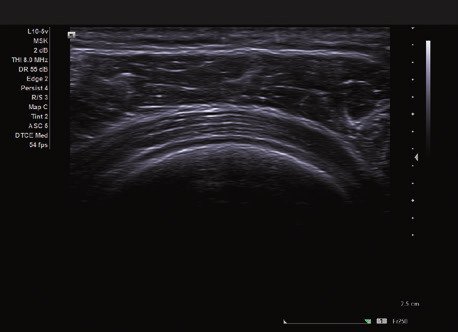

Das ACUSON NX2 Ultraschallsystem besitzt eine zukunftsfähige digitale Plattform mit nahezu unerreichter Bildqualität und sorgt für effiziente und zuverlässige Diagnosedaten. Die Vielseitigkeit des Ultraschallsystems wird mit einem großen kompatiblen Portfolio an Schallköpfen gedeckt, und so ist für jeden Anwendungsbereich etwas dabei. Die Bedienkonsole ist intuitiv aufgebaut und optimiert und erlaubt bis zu vier nach vorne gerichteten Schallkopfanschlüssen für eine enorme Effizienz und schnellen Workflow. So lassen sich bei der fetalen Bildgebung außergewöhnlich detailgetreue Darstellungen des Fetus im Gesicht zeigen oder durch die herausragende Farbdopplersensitivität bei der Darstellung der kleinen Gefäße des zystischen Schilddrüsenknotens kleinste Details erkennen. Weiterhin besticht das NX2 mit einfacher Aufrüstbarkeit bei wachsenden Anforderungen für Ihre zukünftigen Anwendungen und kompatible skalierbare Schallköpfe verringern ihren Kapitaleinsatz um bis zu 31 %.